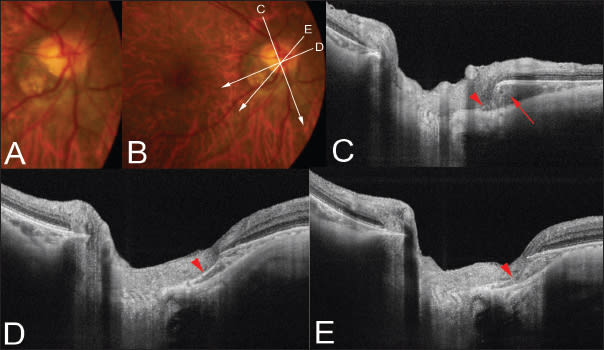

Figure 2. Peripapillary intrachoroidal cavitation. A. Color fundus photograph showing a tilted optic disc and temporal conus. A yellowish-orange lesion suggestive of ICC is not obvious in this patient. B. Scanned lines by swept-source OCT are indicated as lines with arrows. C. OCT slice scanned along the line in B shows the ICC (arrow) as thickening of the choroid below the optic nerve. The remnants of the border tissue of Jacoby are observed (arrowhead). D. OCT slice scanned along the line in B shows the ICC as a stretching of the border of the tissue of Jacoby (arrowhead). E. The stretched border of the tissue of Jacoby seems to be disrupted in this section (arrowhead).

In eyes with no inner retinal defect at the inferior border of the tilted optic disc, there was triangular thickening of the choroid at the base, near the border of the optic nerve (Figure 2). The base of this triangular choroidal thickening seemed to be associated with stretching of the region between the choroid and the optic nerve, a location where the bordering tissue of Jacoby is originally seen (Figure 2).

Furthermore, in more severe cases, a defect in the bordering tissue of Jacoby was seen (Figure 2). The fluid space was observed within the ICC, and there was direct communication between vitreous cavity and the ICC through the inner retinal defect at ICC margin (Figure 1).